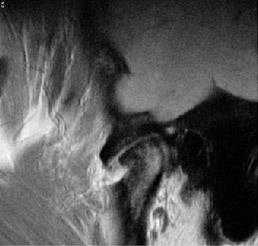

Косо-сагиттальная проекция с закрытым ртом. Нормальный ВНЧС.

Суставной диск не дислоцирован, задняя его часть находится на 12 часах циферблата мыщелка.

Нормальная мобильность диска

Позиция с открытым ртом. Мыщелок сместился вентрально, на уровень суставной ямки. При этом суставной диск сохранил нормальное положение интерпозиции, не давая костным структурам напрямую контактировать друг с другом.